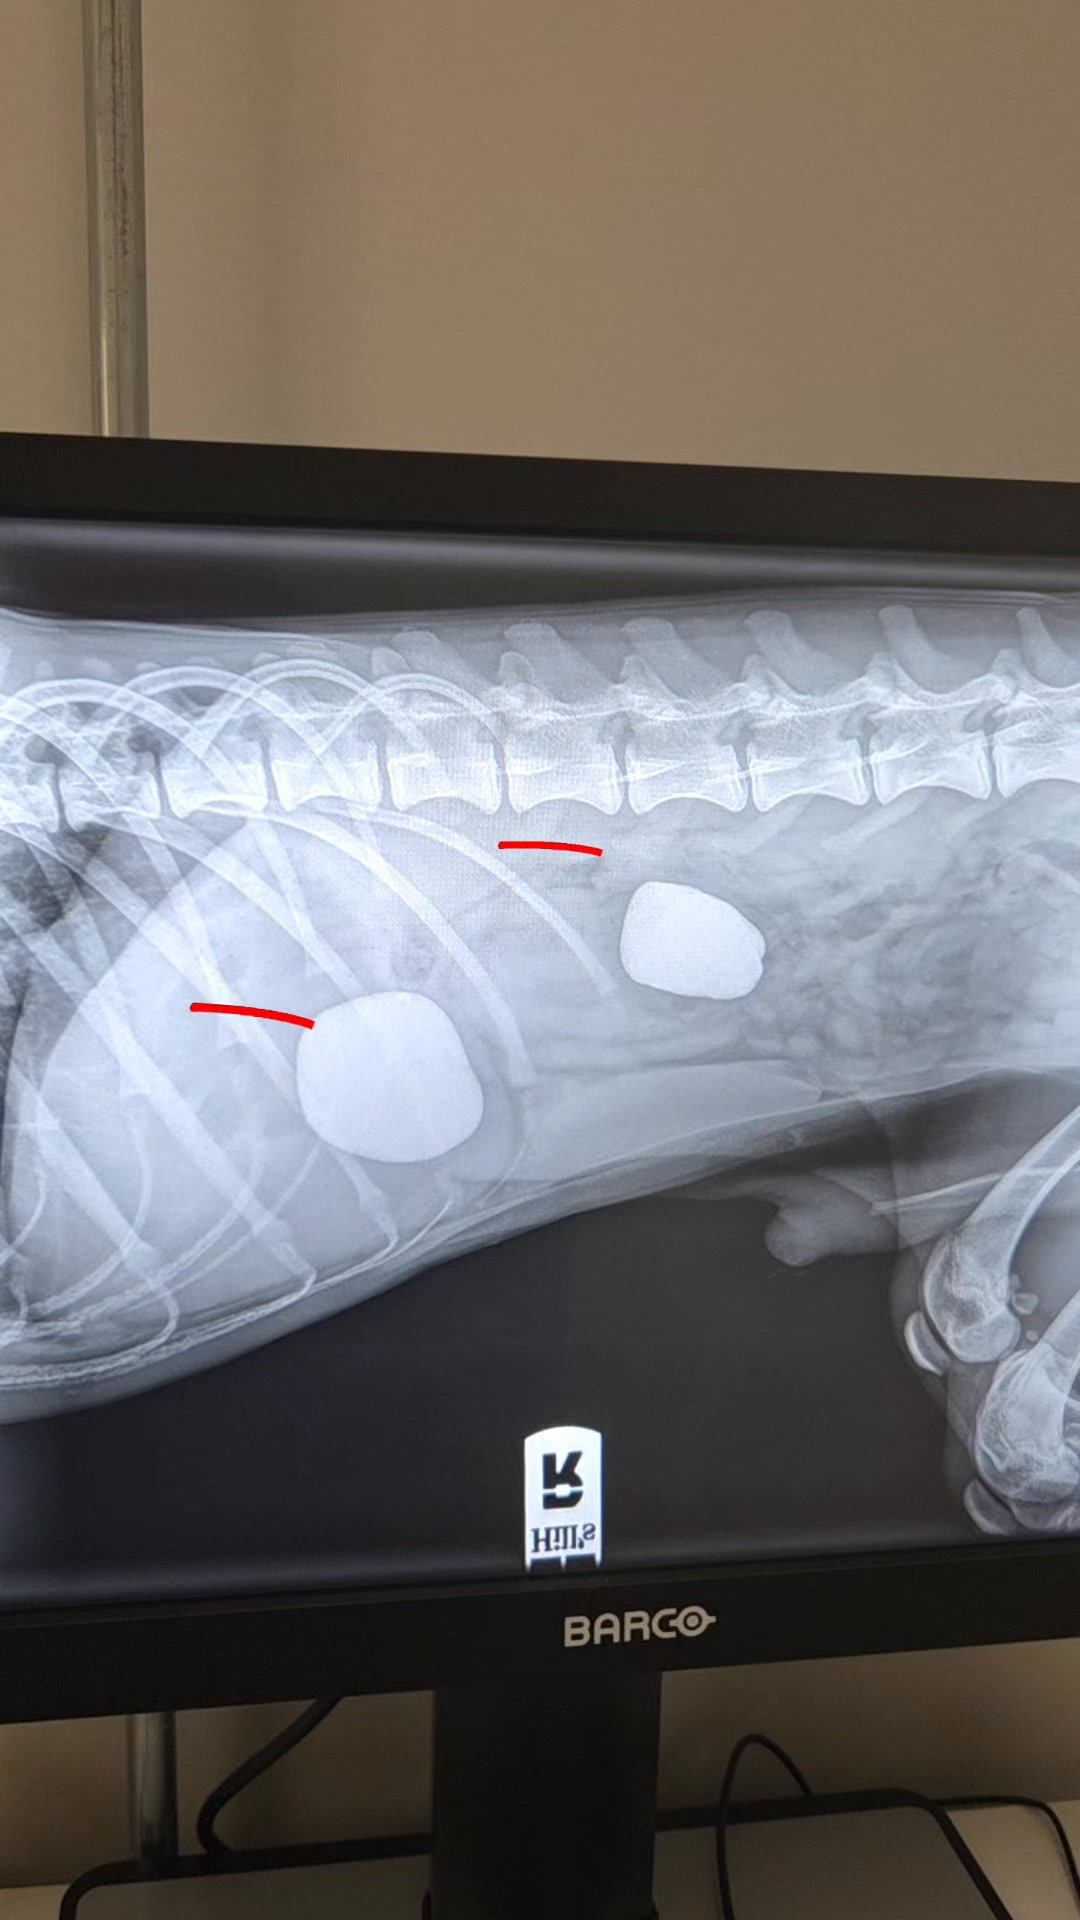

I slutningen af januar kom han ind til os, da han havde tabt sig og var begyndt at kaste op. Røntgenbillederne afslørede hurtigt årsagen: to store sten i maven